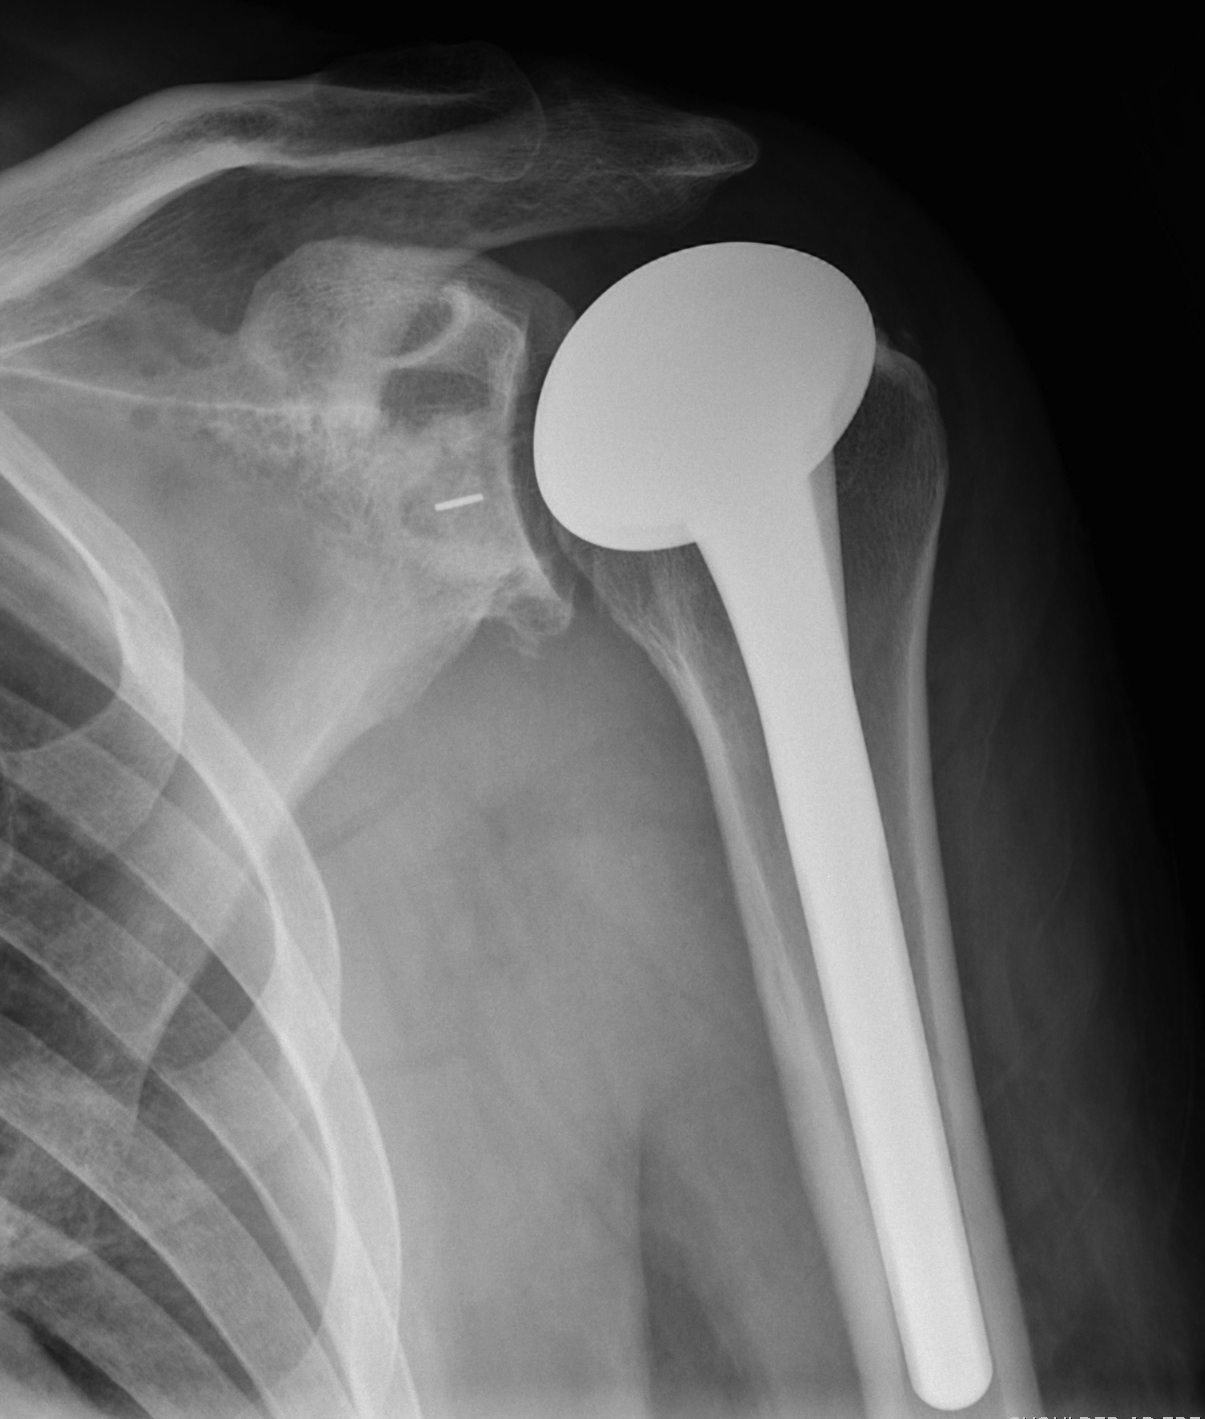

Subscapularis failure

Rotator cuff failure

Instability

Infection

Periprosthetic fracture

Aseptic loosening

Neurological injury

Parada et al. J Should Elbow Surg 2021

- 2224 aTSA complication rate 11%, revision rate 5.6%

Background

Indications

RA

OA

AVN

Contra-indications

Infection

Charcot

Paralysis of deltoid

Torn rotator cuff

Insufficient glenoid bone stock